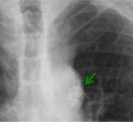

CASO: Paciente con fiebre y tos.

Hallazgos:

- Se observa un aumento de densidad que borra el borde cardiaco derecho, produciendo el signo de la silueta. Ante este hallazgo, localizamos la condensación en el Lóbulo Medio.

- Sin otros hallazgos.

SIGNO DE LA SILUETA: Es el más conocido y clásico de los signos radiológicos, y permite reconocer la localización de lesiones pulmonares. No es un signo específico de lesión alveolar, ya que puede verse en tumores, abscesos y otras lesiones. Más que un signo indicador de patología es un signo localizador. El signo de la silueta se refiere a que cualquier opacidad pulmonar que esté en contacto con el borde cardíaco, la aorta o el diafragma, borrará su contorno; por el contrario, una lesión que no esté en contigüidad con estas estructuras, no borrará su contorno (para ver más: http://album-de-signos-radiologicos.com/category/lesion-alveolar/).